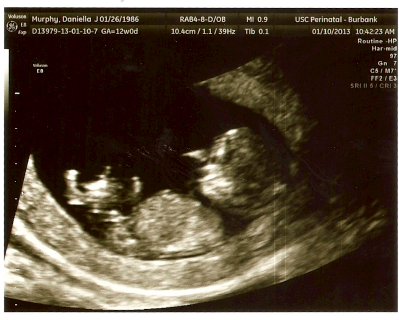

We told our parents and families on Christmas. We told Merfman’s parents on Christmas Eve, and my family on Christmas Morning. We gave each of our Mom’s a card and inside the card was a copy of the above ultrasound and we wrote “Merfbaby, coming July 2013.” Everyone was really happy, it’s the first grandchild on my family’s side, and oh has Momma-son been waiting ever so patiently to be a Grandma! Merfbaby will even have 2 Great Grandparents!

I had two more ultrasounds on my 12 week mark – my rollover happens on Thursdays. I’ve had my blood work, and the first part of the Down Syndrom Screening and everything is looking good. I was really fun to see Merfbaby at the 12 week appointment, it looks like a BABY now! I had one ultrasound in the morning, and Merfbaby was sleeping on its back. After some poking from the tech Merfbaby squirmed and then rolled over with its back to us. My second appointment was after lunch (and a PopTart) and Merfbaby was jumping all over the place! I promise I’m eating healthy though :)